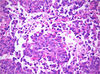

29 yo M w/ 20cm R pelvic mass

Angiosarcoma

- Day of:

- Lots of blood, fibrosis

- RBCs extravasated

- Lots of large, dilated vascular spaces and increased small vessels

- Infiltration growth pattern

- Cells appear pleomorphic, spindled and hyperchromatic; no prominent nucleoli

- Ddx:

- Kaposi’s

- IHC for HHV8

- Kaposi’s

- Stains:

- vascular:

- CD34

- CD31

- D240 (podoplanin)

- ERG-1

- vascular:

- Spindle cell lesion.

- Occasionally an epithelioid lesion.

- Very many small capillaries of irregular shape lined with:

- Pleomorphic nuclei - important.

- May have hobnail morphology.

- Usually “red” at low power - due to many RBCs - important.

- Pleomorphic nuclei - important.

- Mitoses.

- Cytoplasmic vacuoles.

- Cells trying to form lumina - embryologic.

- Notes:

- Epithelioid variant (with abundant cytoplasm & sheeting architecture) may resemble melanoma or hepatocellular carcinoma.

- DDx:

- Atypical vascular lesion.

- Kaposi sarcoma.

- Anastomosing hemangioma - especiallly in the kidney.

- Poorly differentiated carcinoma.

- Other vascular tumours.